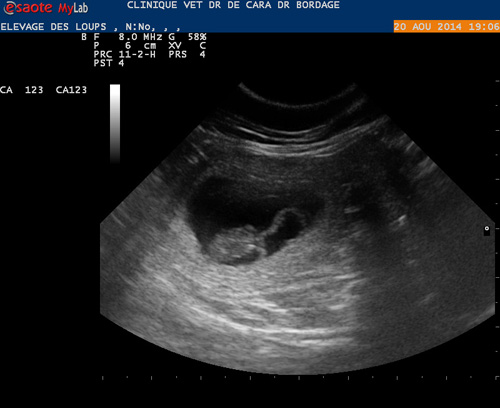

L'échographie pratiquée le 20 août 2014 a confirmé la gestaiton de kajika qui devrait mettre bas vers le 22 septembre prochain.